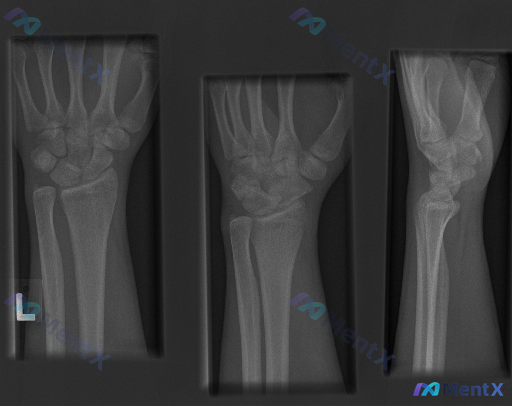

大家好,今天我们来讨论一份左侧腕部外伤后的X光片资料。先给大家看一下三个体位的影像学观察结果: 1. 放射影像-手腕处X光片-正位 (AP View) 骨骼完整性: 桡骨远端: 桡骨远端干骺端见明显骨折线,皮质连续性中断,呈现典型的背侧移位(Colles骨折特征),伴有明显的背侧成角和嵌插表现。桡骨...

整理到一张左手腕及前臂正位X光片及配套的影像学观察内容,先把客观表现列出来,大家一起读片讨论: 影像客观表现 - 骨骼:桡骨远端可见骨质断裂线,涉及关节面,骨折端有移位和粉碎表现,骨皮质连续性中断,断端有台阶样改变;尺骨茎突也可见骨质断裂线,呈撕脱性表现;舟骨、月骨等腕骨形态大致正常;桡尺骨干皮质连...

整理到一份成人左侧前臂及腕部的斜位X光片资料,结合影像描述整理如下: 主要影像表现 1. 骨骼方面: - 左侧桡骨远端干骺端可见骨皮质中断、断裂线,骨折远端向背侧及桡侧移位,有成角畸形,断端有嵌插迹象; - 左侧尺骨茎突可见骨皮质中断,分离较明显; - 舟骨及其他腕骨皮质相对连续,掌骨基底排列尚可。...